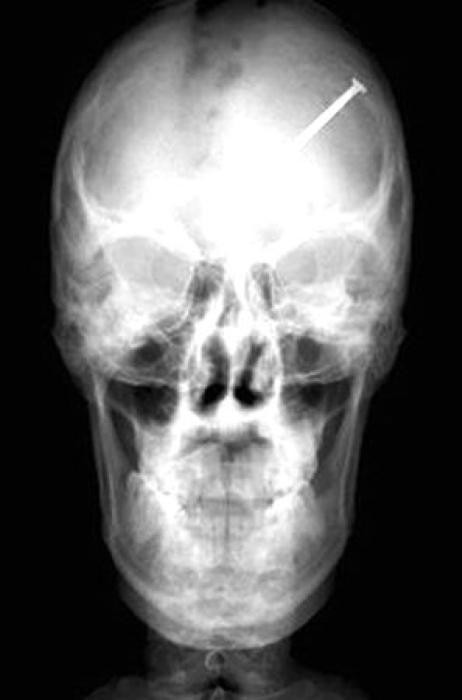

33 radiographies qui prouvent que les gens font des choses douteuses avec leur corps !